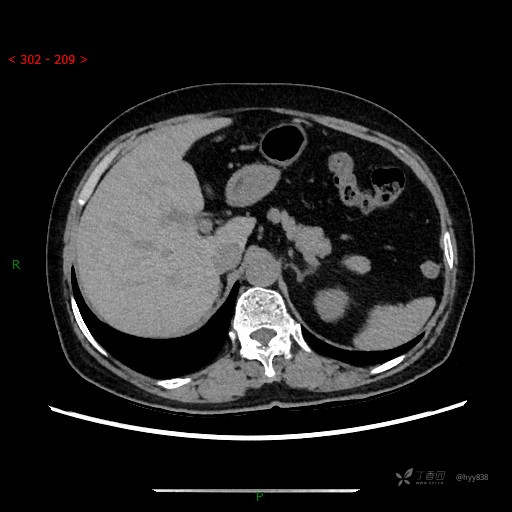

增强动脉期